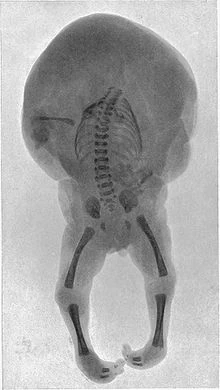

- Takofuusen seems to resemble the symptoms of a birth defect known as Twin Reversed Arterial Perfusion or "TRAP sequence", where one of a pair of birthed twins is severely malformed, generating only a torso and the lower half of a body. According to an article by the Indian journal of radiology and imaging, TRAP sequence has a 1 in 35000 chance of occurring. It only ever occurs in monochorionic (identical) twins, which is interesting because most NPCs that reside in the White Desert have names starting with mono (being short for monochrome), with the White Desert's Japanese name even being that.